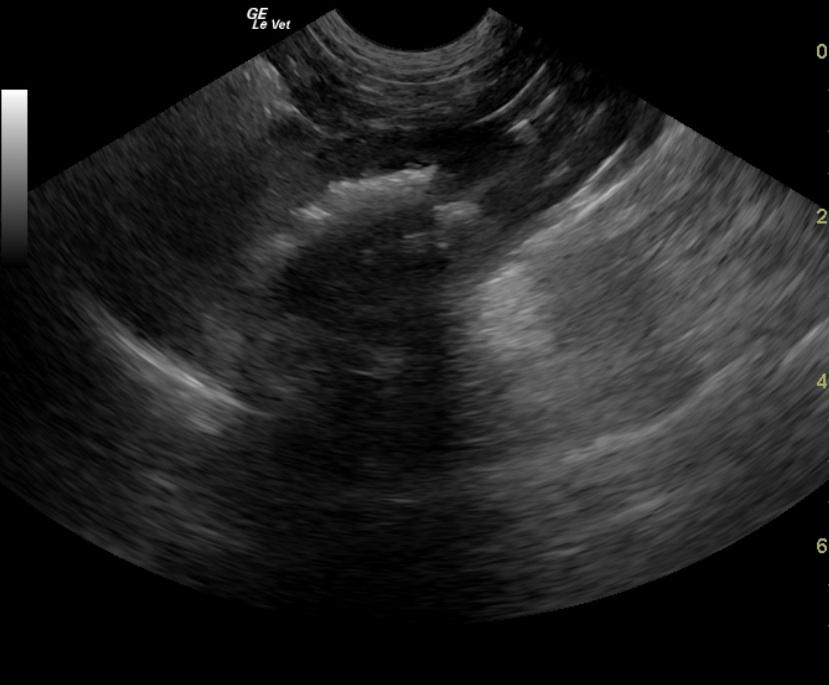

A 4-year-old F Yorkshire Terrier dog was presented at an emergency facility for acute onset disorientation, unresponsiveness, and vomiting. On physical examination, she appeared blind and was disoriented. Abnormalities on CBC and blood chemistry were low MCV and hypocholesterolemia. The patient was treated with K/D diet. Recheck blood work a month later showed alkaline phosphatase normalized and a normal WBC. Eight months later, the owner reported that the patient was still vomiting 1-2 times a week and getting Lactulose. CBC showed low MCV and MCHC.

A 4-year-old F Yorkshire Terrier dog was presented at an emergency facility for acute onset disorientation, unresponsiveness, and vomiting. On physical examination, she appeared blind and was disoriented. Abnormalities on CBC and blood chemistry were low MCV and hypocholesterolemia. The patient was treated with K/D diet. Recheck blood work a month later showed alkaline phosphatase normalized and a normal WBC. Eight months later, the owner reported that the patient was still vomiting 1-2 times a week and getting Lactulose. CBC showed low MCV and MCHC. The only change on blood chemistry was elevated ALP activity. Nutrical was added to the therapy. Two weeks later, the patient was presented for vomiting. On physical examination, the patient was febrile and slightly disoriented. The patient was treated with metronidazole and L/D diet. The following morning the owner reported that the patient was back to normal.